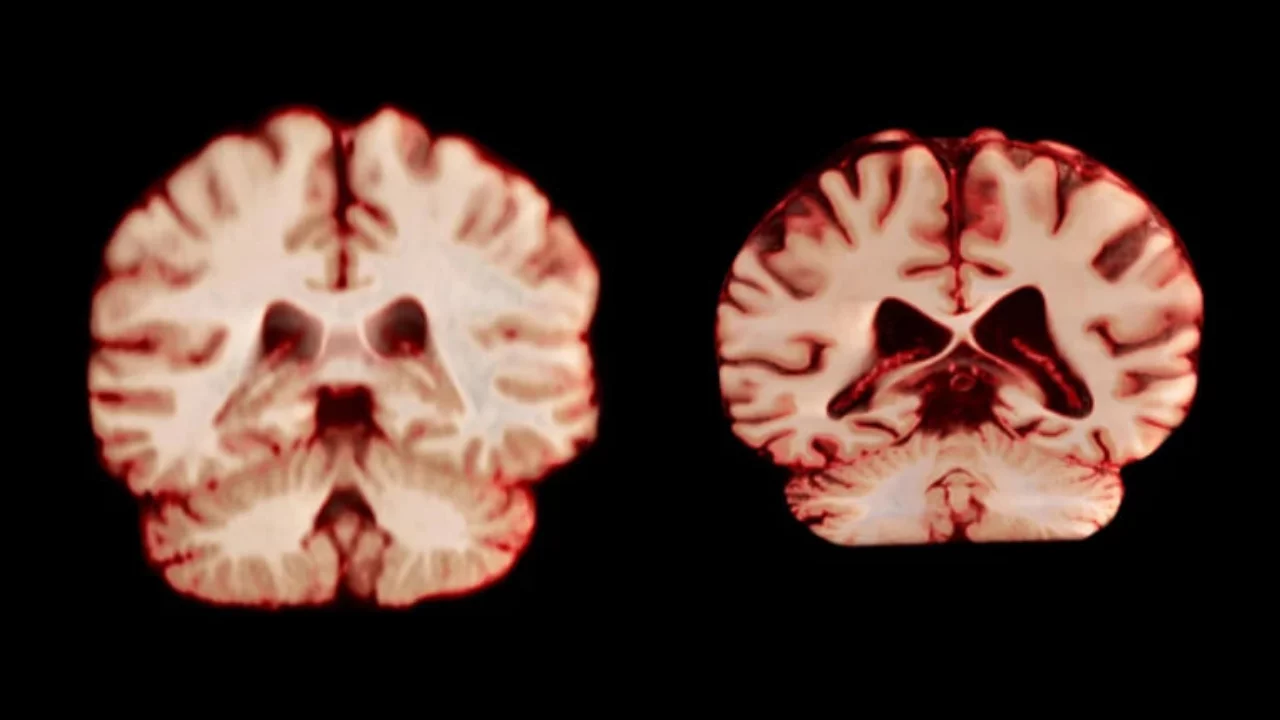

В рамках исследования специалисты проанализировали более 12,5 тысячи снимков магнитно-резонансной томографии (МРТ) 4726 человек. У каждого участника было сделано как минимум два снимка с интервалом примерно в три года.

Результаты показали, что у мужчин объем мозга сокращается сильнее, чем у женщин. В частности, в постцентральной коре — участке мозга, отвечающем за ощущения и движения, — у мужчин наблюдалось уменьшение примерно на 2 процента в год. У женщин этот показатель составил 1,2 процента.

По мнению ученых, это объясняет, почему мужчины стареют быстрее и живут меньше. Тем не менее, болезнь Альцгеймера у женщин по-прежнему диагностируется почти в два раза чаще.